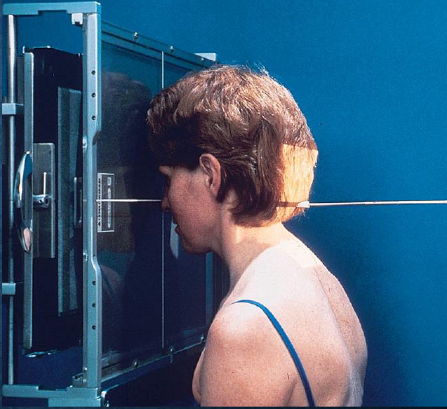

SMV (Schuller) skull

patient position:

upright (seated) or supine (torso elevated)

part position:

MSP centered to midline

MSP perpendicular to IR

IOML parallel with IR

patient hyperextends neck and rests head on vertex

respiration suspended

CR:

perpendicular through sella turcica and IOML

enters MSP of throat between angles of mandible (gonion)

passes through a point ¾ inch anterior to the level of the EAM

collimation:

½ inch beyond the shadow of the tip of the nose and 1 inch beyond the lateral borders